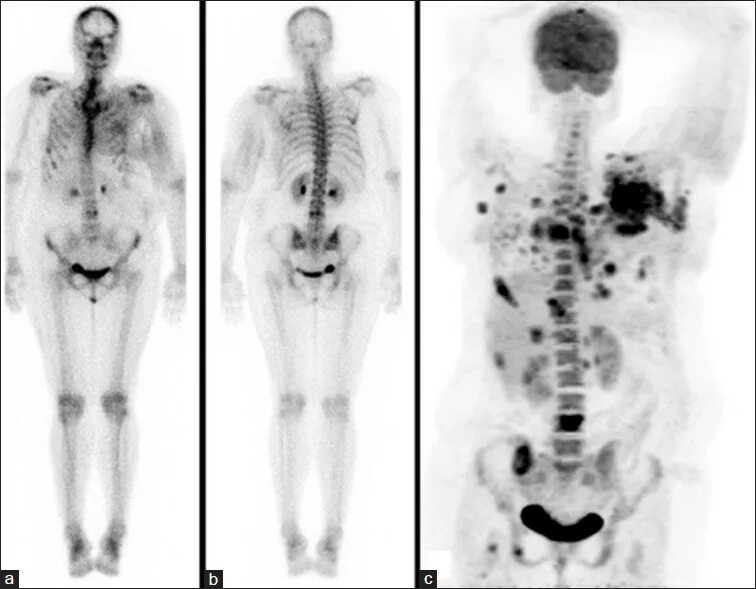

Метастазы костей скелета